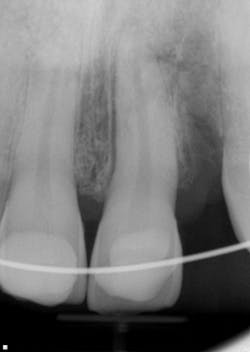

The six-week post-trauma follow-up (figure 5):

- Teeth Nos. 6 through 8 all tested vital.

- No. 9 appeared to continue stabilizing within the bone.

- We changed out the calcium hydroxide dressing.

- Another four to six weeks of healing was recommended, with subsequent completion of root canal and orthodontics wire removal.

Figure 5